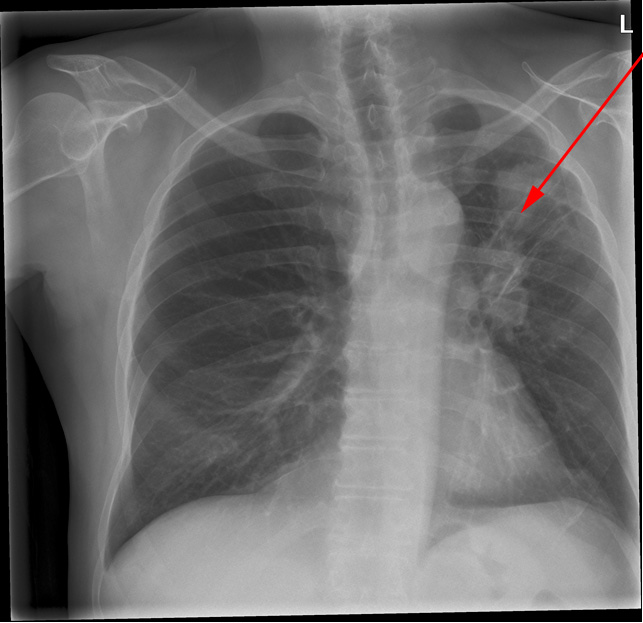

Røntgen (oven for) og CT-optagelse (neden for) af den samme patients lunger med få dages mellemrum. Begge billeder viser stor lungetumor i venstre overlap (røde pile).